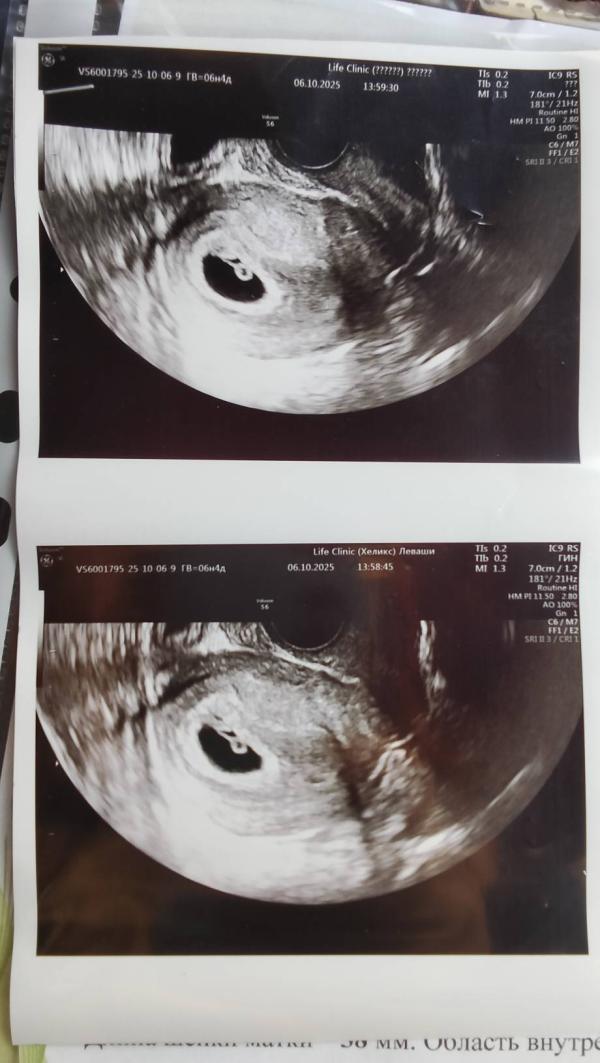

Не услышали сердцебиение на УЗИ: что делать и когда ждать

1 узи, волнительно , не смогла сердечко послушать 🥺

Сказали на следующем приëме, жду с нетерпением